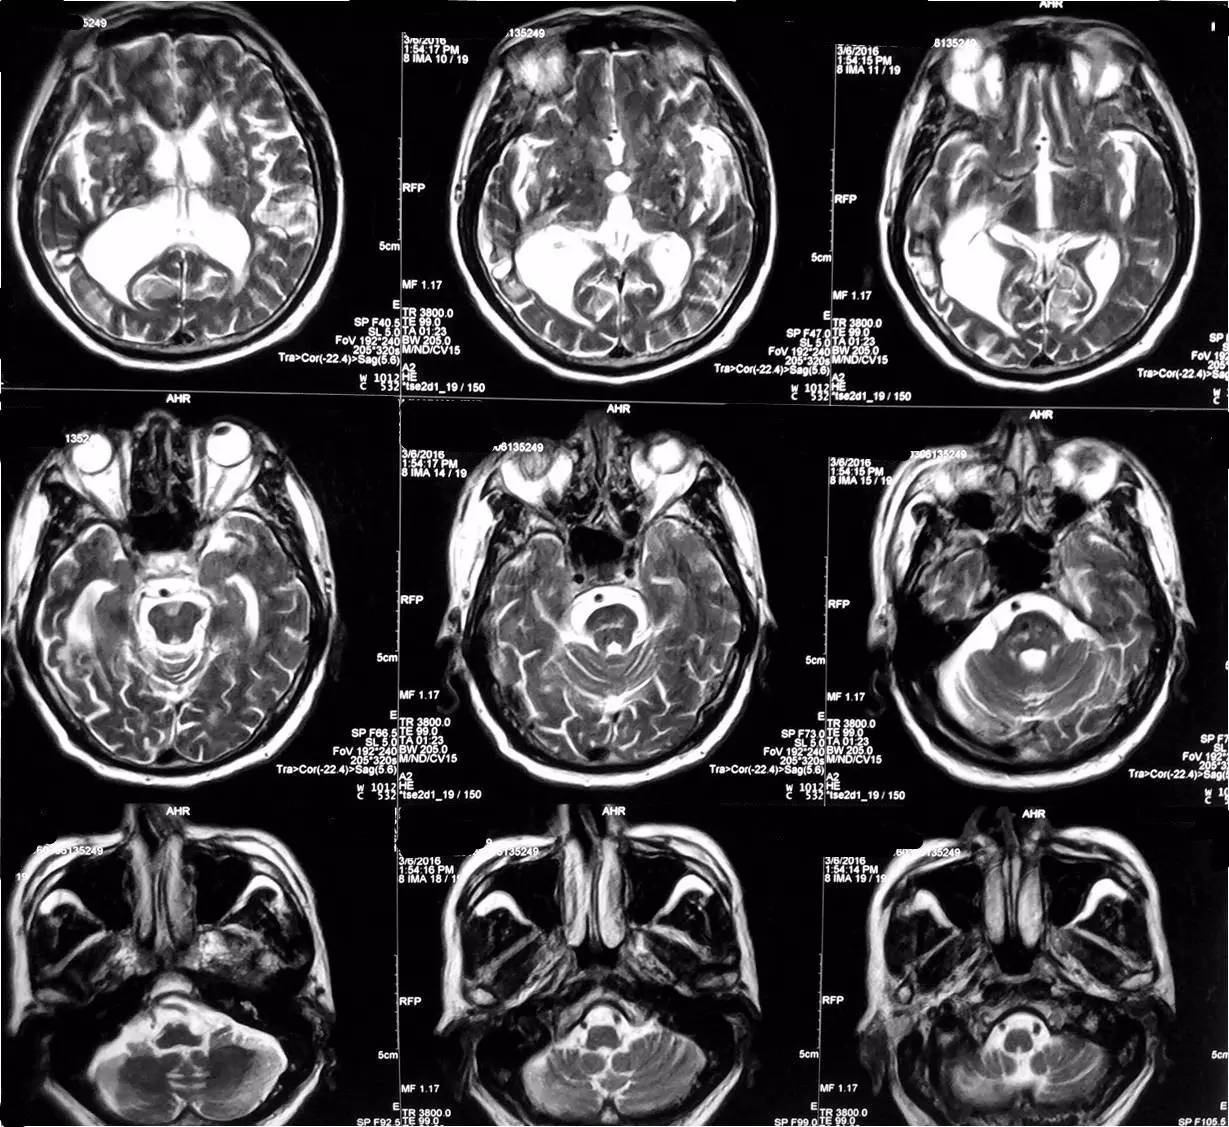

2016-3-6 头MRI+MRA示右侧基底节亚急性脑梗死;双基底节、放射冠、丘脑、脑干、右侧颞枕叶多发脑梗死,部分软化灶形成;脑萎缩改变;MRA符合动脉硬化改变。

▼头MRI(2016-3-6)